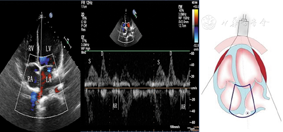

图13

标准心尖四腔切面引导脉冲波组织多普勒取样二尖瓣侧壁瓣环舒张期组织运动速度峰值e峰和a峰测量方法

图14

标准心尖四腔切面引导脉冲波组织多普勒取样二尖瓣室间隔瓣环舒张期组织运动速度峰值e峰和a峰测量方法